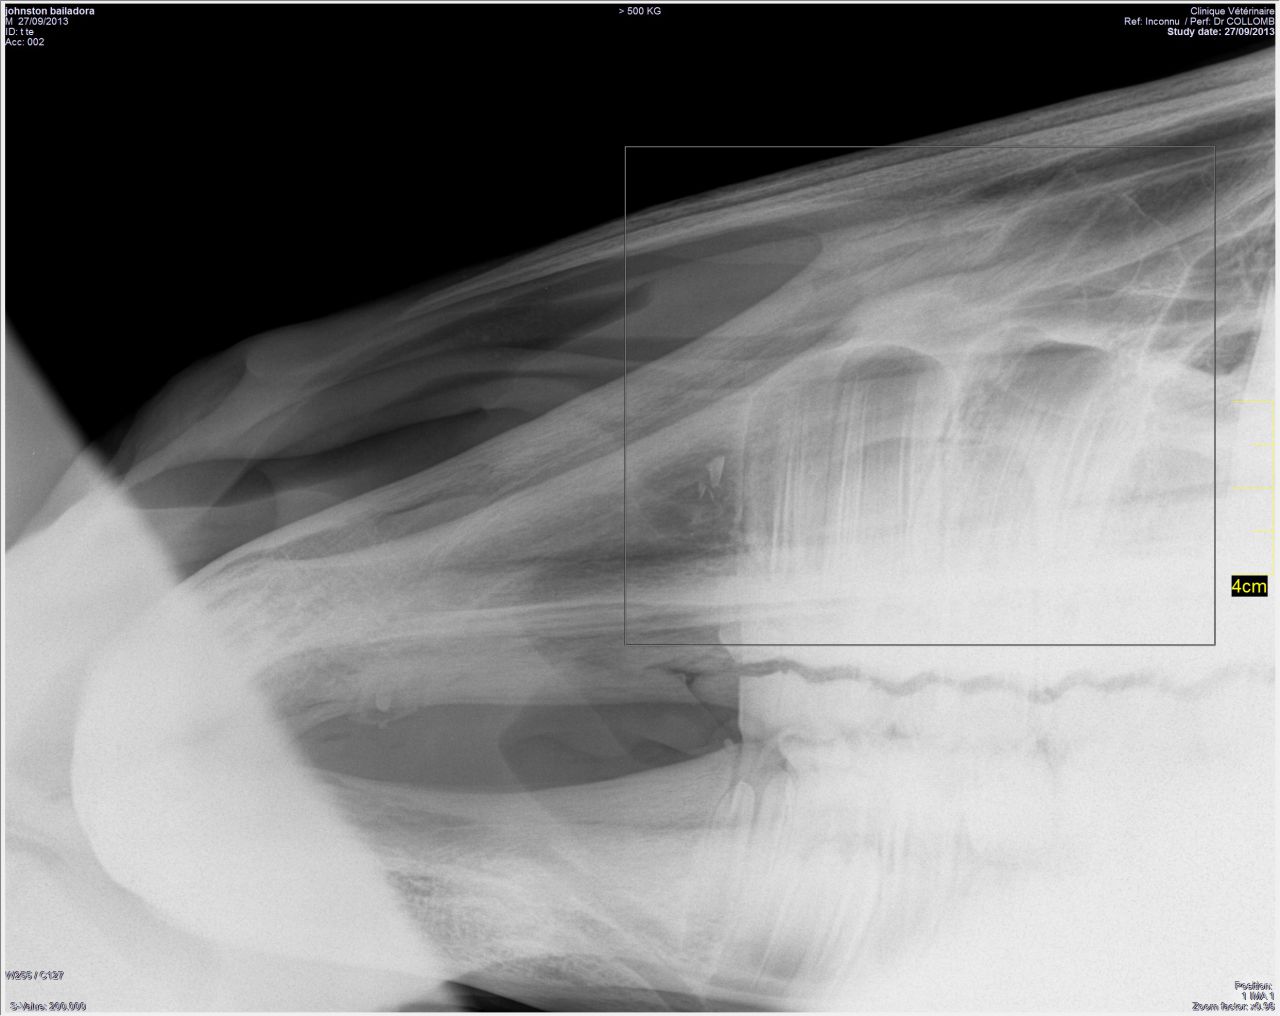

| Dire merci | Et les photos de la bossue! (on voit légèrement la bosse)![]() Et les radios! ![]() ![]() ![]() |